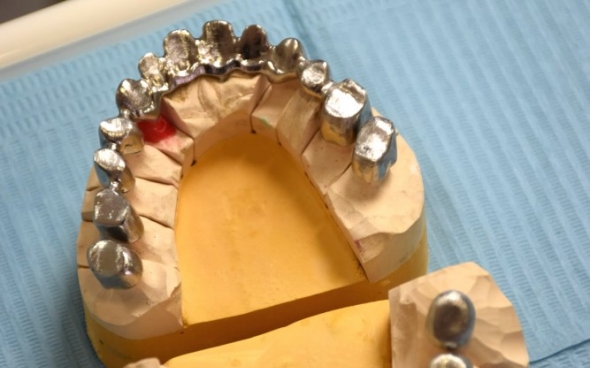

Teleskopierender Zahnersatz

Der 75 jährige deutsche Patient machte sich mit einem Lückengebiss und einem herausnehmbaren Zahnersatz in schlechtem Zustand vorstellig. Mehrere Zähne mussten extrahiert werden.